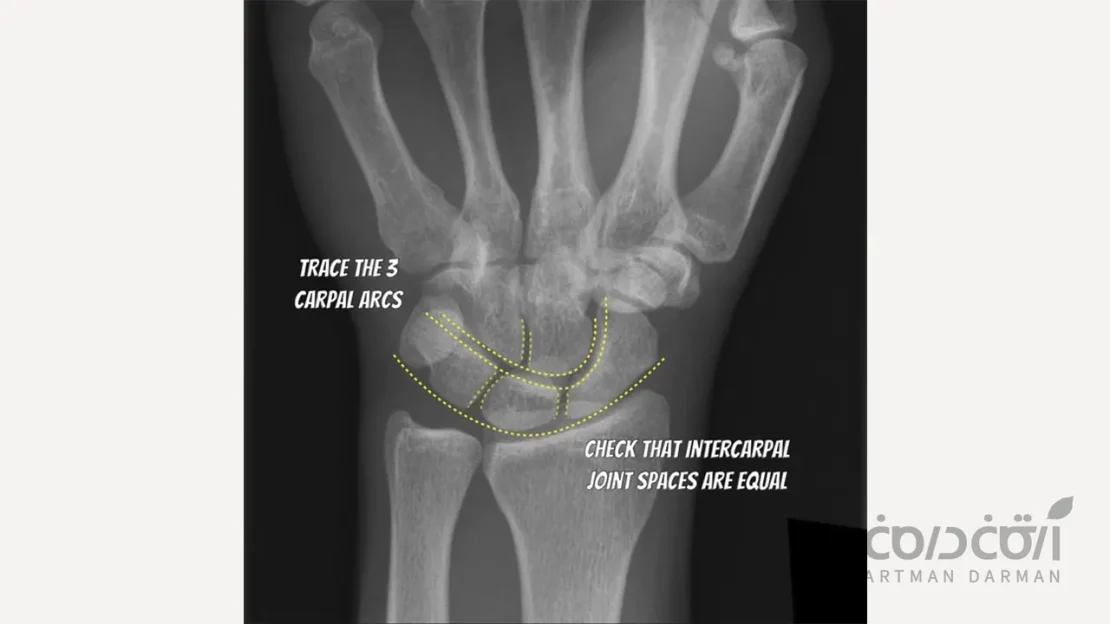

رادیوگرافی مچ دست (Hand-Wrist Radiograph)

این روش نیز سن استخوانی فرد را نشان می دهد. با مشاهده وضعیت صفحات رشد (Epiphyseal Plates) در استخوان های مچ دست و انگشتان، می توان تشخیص داد که آیا فرد جهش رشدی بلوغ را به پایان رسانده است یا خیر. جوش خوردن این صفحات، نشانه ای قابل اعتماد از توقف رشد عمومی بدن است.